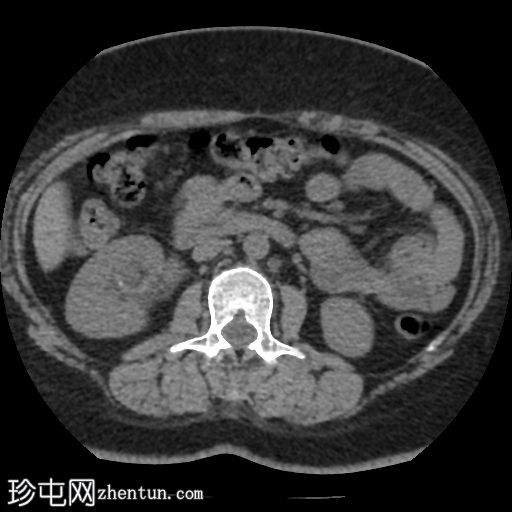

冠状位

平扫

平扫CT显示右肾盂内有一结石,大小约17 × 16 mm,CT值1115 HU,引起轻度肾积水。右肾下盏内可见另一小结石,大小约8 × 4 mm,CT值611 HU。

子宫前壁可见一软组织肿块,大小29 × 24 mm,与子宫肌层密度相近,呈外生性生长,无钙化或脂肪成分。

其他腹部器官CT检查结果正常。

非增强 CT 对检测泌尿系统结石具有很高的敏感性。大多数结石为放射性不透光结石,其衰减值因成分而异。本例中,较大的右肾盂结石的衰减值为 1115 HU,符合鸟粪石的特征,鸟粪石通常与感染有关,在女性中更为常见,并且可能形成鹿角状结石。

较小的下肾盏结石的衰减值为 611 HU,提示为草酸钙结石。识别结石成分对于指导治疗和预防具有重要的临床意义。

关于子宫病变,其主要符合浆膜下肌瘤的特征。建议进行经阴道超声检查。